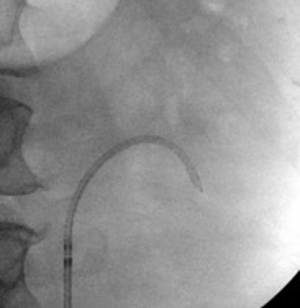

The patient underwent a right ureteroscopy and laser lithotripsy. Using a semi-rigid ureteroscope, a large impacted and obstructing stone was encountered. A hydrophilic wire was advanced past the stone into the renal pelvis. A ureteral catheter was advanced over the hydrophilic wire into the renal pelvis under fluoroscopic guidance, and the hydrophilic wire was exchanged for a super-stiff wire. Due to edema and tortuosity of the ureter, the semi rigid ureteroscope could not safely maintain visualization of the stone. Therefore, a 12/14 Fr x 28 cm ureteral access sheath was advanced to the level of the stone and a flexible ureteroscope was advanced to the level of the stone, to allow optimal visualization and laser lithotripsy.

A 200μm thulium laser fiber was advanced through the ureteroscope in conjunction with the TFL (Soltive™ SuperPulsed Laser System, Olympus) platform. Low energy settings (1J, 2 Hz) were used with short pulse, and fragmentation technique to minimize the risk of ureteral injury and reduce stone retropulsion. Pauses every 30 seconds were taken during the procedure to avoid thermal injury to the ureter. Stone fragments were successfully retrieved using a basket. After all stone fragments were extracted, there was no evidence of ureteral injury or residual stones.